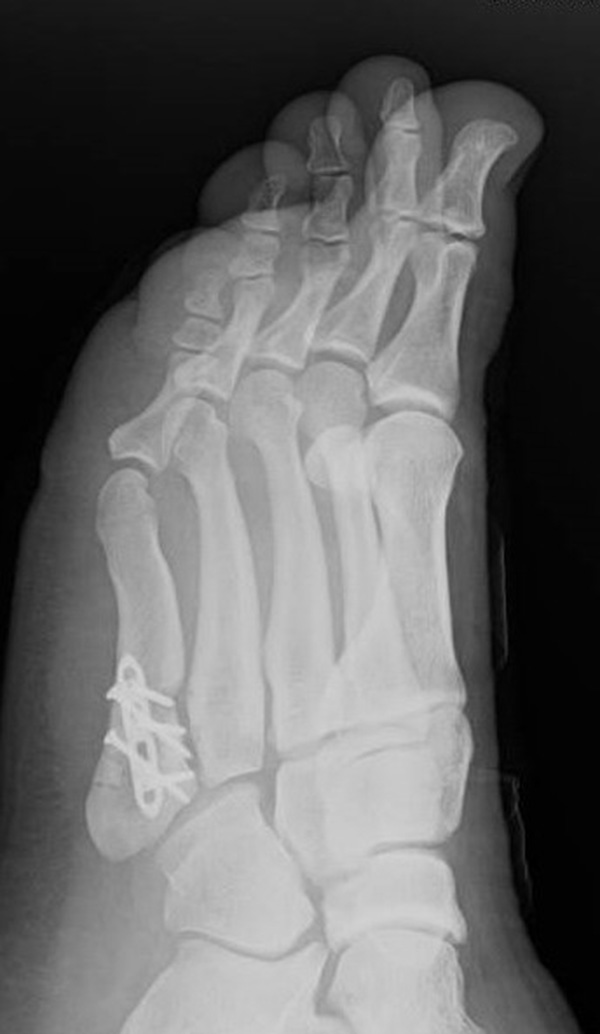

Abb. 3a, b: Präoperatives (a) und postoperatives (b) Röntgenbild bei Korrektur einer Typ I Deformität durch eine Exostosenabtragung.

Abb. 12a: Typ III Deformität präoperativ im belasteten dp Röntgenbild.

Abb. 12b: Dorsoplantare Röntgenkontrolle nach medial schließender Osteotomie mit Schraubenosteosynthese.

Abb. 12c: Schrägaufnahme nach medial schließender Osteotomie mit Schraubenosteosynthese.